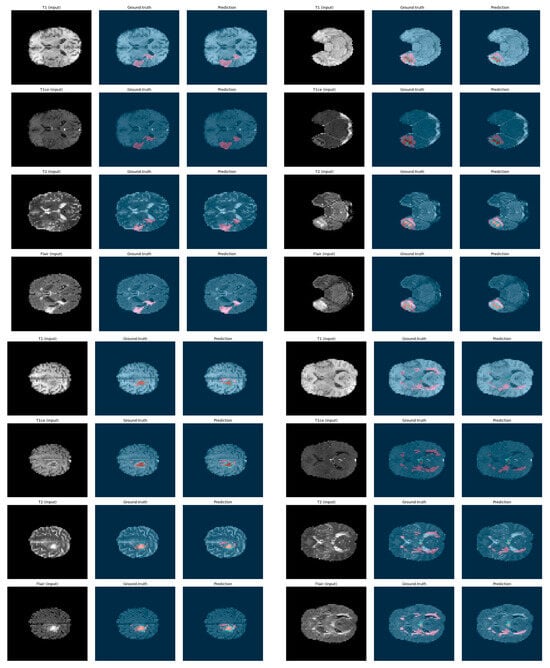

5.3. Qualitative Visualization